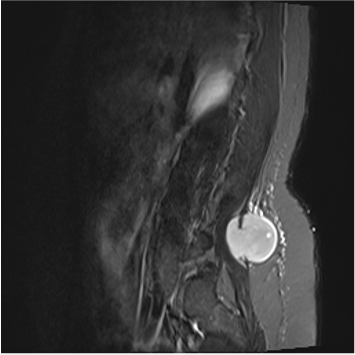

Bilateral Extracranial Internal Carotid Artery Dissection: Interventional Management – A Case Report

Payam Sasannejad, Amir Khanmirzaei, Mohsen Soltani, Bahar Karimikhoshnoudian, Reza Gorji, Houman Baharvahdat, Soheil Shokri Shakib, Maryam Payere